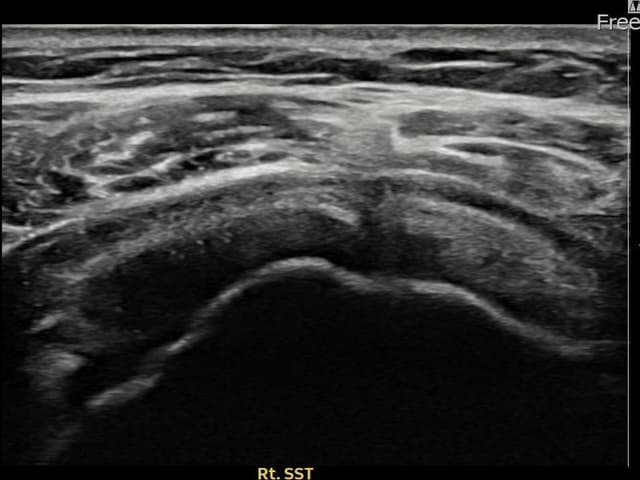

右侧 冈上肌腱 石灰化肌腱炎

14mm × 10mm